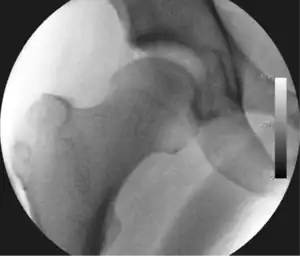

The procedure is performed with the patient asleep (general anaesthetic) or under spinal anaesthesia. There are two widely used methods, one with the patient on their back (supine) and the other on their side (lateral decubitus). Which is used is down to the surgeon's preference. To gain access to the central compartment of the hip joint (between the ball and socket), traction is applied to the affected leg after placing the foot into a special boot. (See fig. 2) There is specifically designed equipment for this, although some surgeons use a 'traction table', initially designed to help in the operative fixation of broken thigh and lower leg bones. The amount of traction (or pull) needed is assessed with the help of fluoroscopy (low-dose portable x-ray). (See fig. 3) It is usually not possible to distract the ball from the socket with traction alone by more than a few millimetres. Once the surgeon is happy that they will be able to gain access to the hip joint (i.e. the ball will distract from the socket by a small amount), the patient is then painted with antiseptic and the surgical drapes applied.

The next step is to insert a fine needle under x-ray guidance into the hip joint. This breaks the 'suction seal' of the joint and allows further distraction if necessary (see fig 4). The surgeon wishes to see the ball move out the socket by approximately 1 cm, so that access to the hip joint can be achieved with minimal risk of damage to the joint surfaces. Most surgeons will inject fluid into the joint at this stage, again to ensure that there is enough space between the ball and socket for safe instrument access. This needle is then removed. The next step is placement of the 'portals', or the small holes made to pass instruments into the joint. This is achieved by again passing a fresh hollow needle into the joint under x-ray control, usually in a slightly different position. The reason for this is so the surgeon can ensure that the needle, and subsequent cannulae do not penetrate and damage the acetabular labrum or cartilage joint surfaces (see fig. 5). Again, surgeons will have their own preferences as to their preferred placement. Through this hollow needle, a long thin flexible guide wire is passed into the joint, and the needle is removed over it, leaving the guide wire in situ. A small cut in the skin is made around the wire, to allow for larger cannulae to be placed over the wire through the portal. The wire therefore guides the larger cannulae into the joint. The most common external diameters of cannulae used are between 4.5 and 5.5 mm. Once the surgeon is satisfied that the cannula is in the correct position, by a combination of feel and x-ray guidance, the guide wire can be withdrawn. Once the first portal is correctly placed, any further portals may be created once the camera is in position, to ensure that they are placed with minimal risk to the joint surfaces. This process can be repeated to gain as many points of entry to the hip joint as the surgeon requires, normally between two and four. Certain of these entry points will be used for the viewing arthroscope and others for operating instruments.